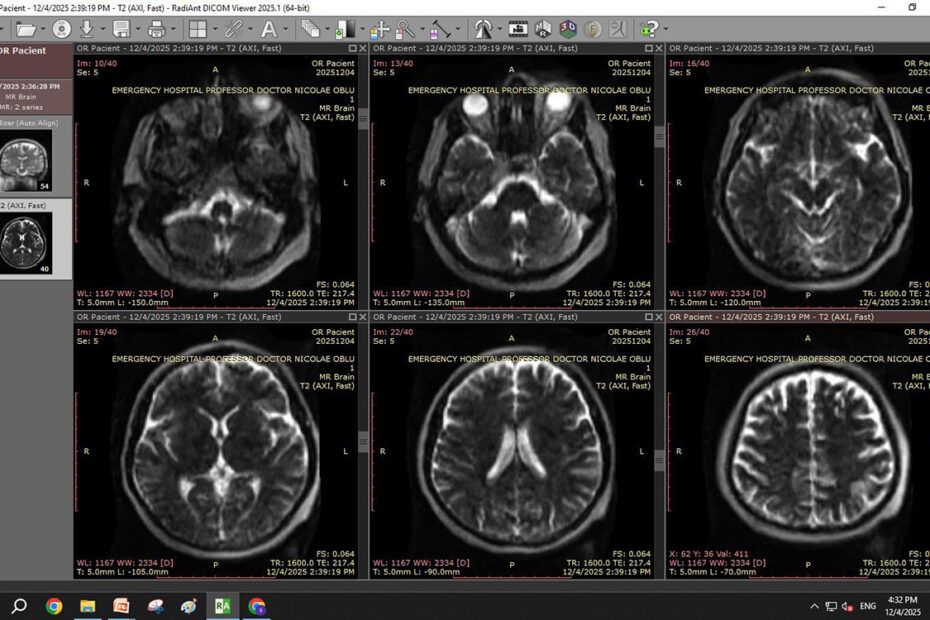

Pentru a demonstra eficiența echipamentului, ministrul Sănătății, Alexandru Rogobete, a efectuat el însuși o scanare în noul sistem RMN mobil. Rezultatul: doar 6 minute — un contrast puternic față de cele aproximativ 60 de minute necesare pentru un RMN clasic.

„Mi-am făcut primul RMN în primul sistem RMN mobil din România: 6 minute. Da, 6 minute, față de cele 60 de minute ale unui RMN clasic. Este incredibil unde putem ajunge când investim corect și cu viziune”, a declarat Rogobete.